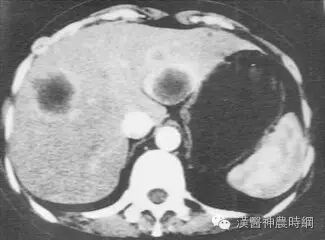

2.计算机X线体层扫描(CT)  CT是一种安全、无创伤、高分辨力的检查方法。对肝癌的定位诊断很有价值。CT能显示肿瘤的大小、位置、数目及与周围脏器和大血管的关系,可检出1cm左右的早期肝癌。并有助于了解是否伴发肝外转移,如肝门淋巴结,胰头后淋巴结等。结合增强扫描可以判断病变的性质,对肝癌与肝血管瘤的鉴别有较大的价值。平扫下肝癌多为低密度占位,边缘清晰或模糊,部分有包膜的肝癌可显示晕圈征。较大的肝癌可见更低密度的坏死区,少数肝癌可见钙化。增强扫描有滴注法、大剂量推注、推注加动态扫描等。肝癌在动脉期尤以注药20s内强化最为明显,癌灶密度高于周围肝组织。30~40s后造影剂进入细胞间隙转入实质期,病灶又恢复为低密度,显示更为清晰。近将肝动脉造影与CT检查相结合,开展CT动脉造影(CTA)和CT动脉门脉造影(CTAP),对提高小肝癌的检出率有一定价值。也有人在CT检查前一周经肝动脉插管注入碘化油(lipiodo1),再做CT扫描,这种lipiodol-CT可检出0.5cm的小肝癌。对于<1cm的肝癌,Uchida报告US、CT、肝动脉造影和几种CT检查的分辨力为:US 63%、普通CT 12%、滴注法增强扫描65%、CTA 71%、CTAP 80%、lipiodol-CT 89%。